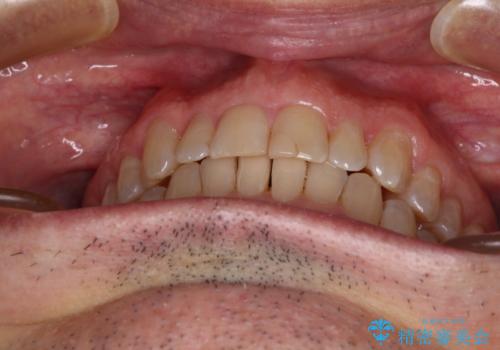

【モニター】前歯のデコボコを治したい インビザライン矯正治療

- 患者様

- 40代男性

- 矯正装置

- インビザライン

- 前歯のデコボコを気にして来院された患者様です。

インビザラインでもワイヤー装置でも対応可能でしたが、仕事の都合で来院回数を減らしたいとのことでインビザラインによる矯正治療を選択されました。

著しく咬合力が強いため、奥歯がしっかりと噛めずに治療が長引くことが懸念されました。

1セット目のインビザラインを使用した際には左右ともに大臼歯が咬み合っていなかったのですが、2セット目できっちりと仕上げることができました。